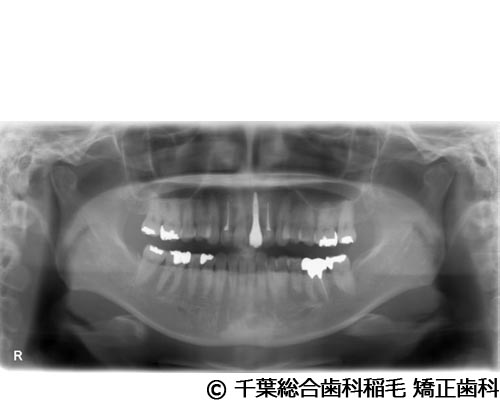

【症例1】下顎大臼歯3本インプラント埋入手術

- 治療前

- 治療後

- 治療名

- 下顎大臼歯3本インプラント埋入手術

- 費用

- 1,400,000円(税込)

- 期間

- 10ヵ月

治療内容

-

患者様の症状

左下第一大臼歯は他院で治療中でしたが、治療がなかなか進まず、他の部位にもお痛みが続いていたため、当院にご相談に来られました。

治療法

左下第一大臼歯は保存が厳しい状態だったため、抜歯となりました。

ご来院時から欠損状態だった右下第一、第二大臼歯も含め、欠損補綴についてお話させていただき、インプラントでの治療を選択されました。 -

治療結果

お痛みも和らぎ、現在も定期検診で拝見させていただいています。

※治療結果は患者様によって個人差があります。